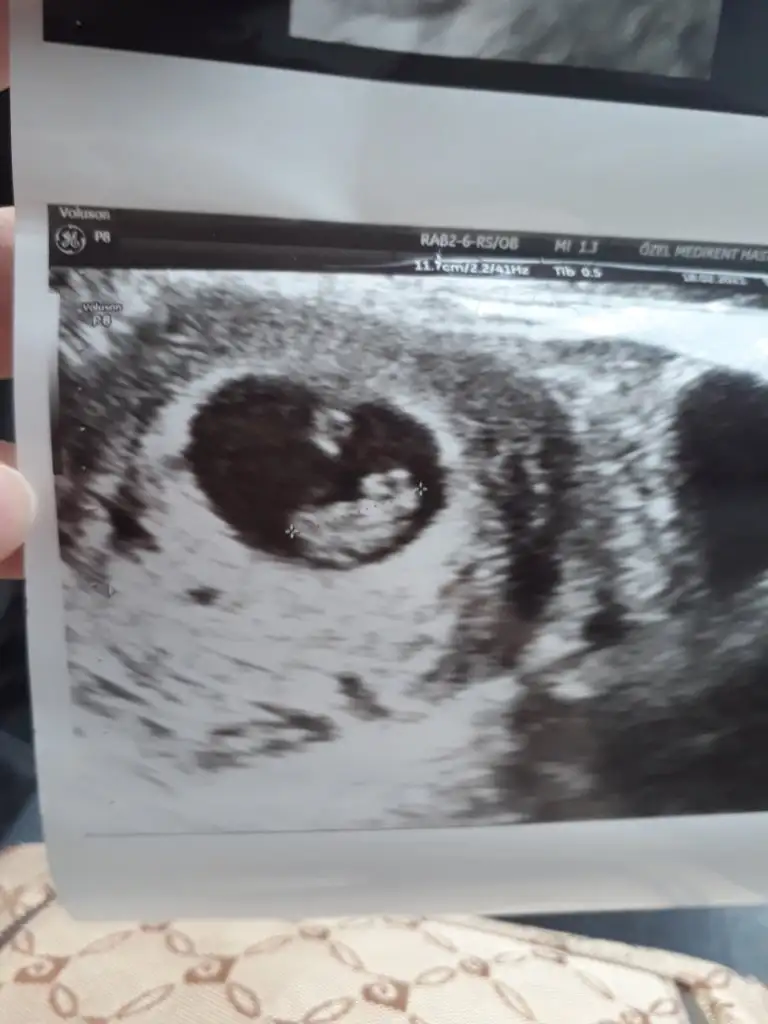

Ya bir şey sorabilir miyim doktora gittiğimizde 9+2 haftalıkken benim bebek baş aşağı idi bacakları havada karnıma doğruydu yüzü 4d ultrasonda öyle gördük tek benimki mi öyle merak ettim Birde hareketlerini gördük doktora sordum normal her şey dedi ama merak ettim Duruşu biraz Farklı geldi 😄